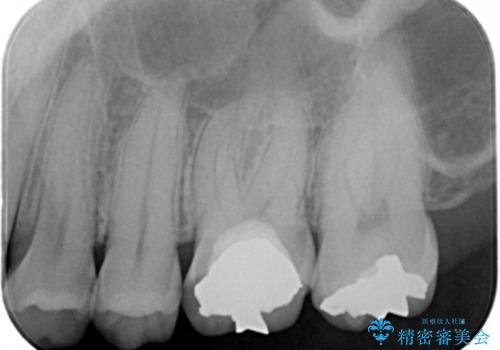

- 詰め物が欠けたとの事で来院。

口腔内を確認したところ詰め物が欠けていたのではなく歯質がう蝕により欠けていました。

拡大鏡下でう蝕を全て取り除き、フルジルコニアクラウンで治療を行いました。